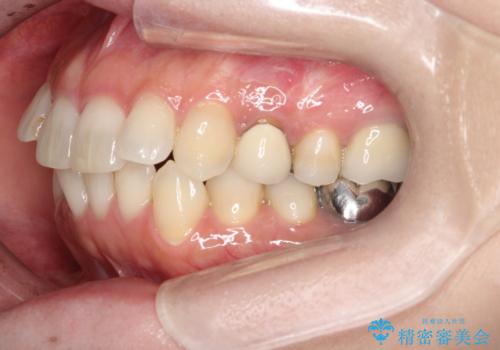

- 前歯のがたつきを主訴に来院されました。

なるべく目立たない矯正をご希望されたので、インビザラインにて治療することとなりました。